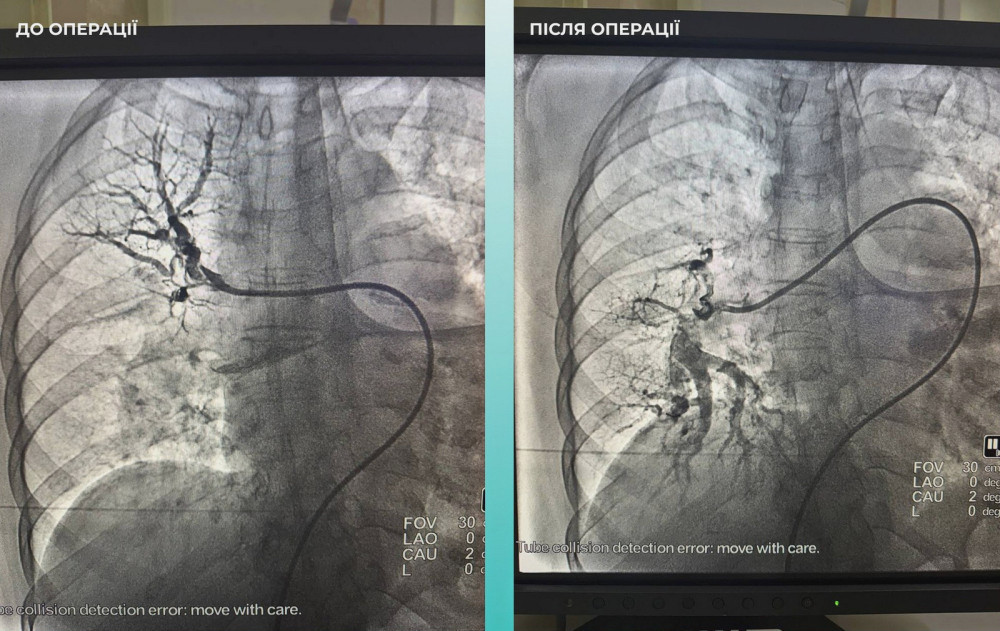

Мультидисциплинарная команда врачей приняла важное решение провести одновременную тромбектонию в мозговой и легочной артериях.

Операция прошла успешно. В настоящее время пациентка чувствует себя лучше: она в сознании и может двигать конечностями.